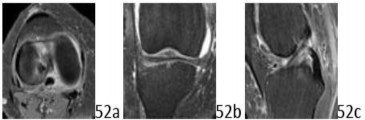

52a 52b 52c Figures 52a through 52c show the axial, coronal, and sagittal T2-weighted MRI scans respectively of a knee. The highlighted structure represents what anatomic finding?

DISCUSSION: The images show a transverse meniscal ligament, which connects the anterior horns of the medial and lateral menisci. On sagittal images, the interface of this structure with the anterior horn of the lateral meniscus often simulates a tear. Following this structure over several successive images is helpful in identifying it as a normal structure. There is no abnormal signal within the menisci to suggest a tear. A meniscofemoral ligament is a posterior structure. A ligamentum mucosum or infrapatellar plica is best seen on the sagittal image and runs from the intercondylar notch to the anterior fat pad. The Preferred Response to Question # 52 is 5.